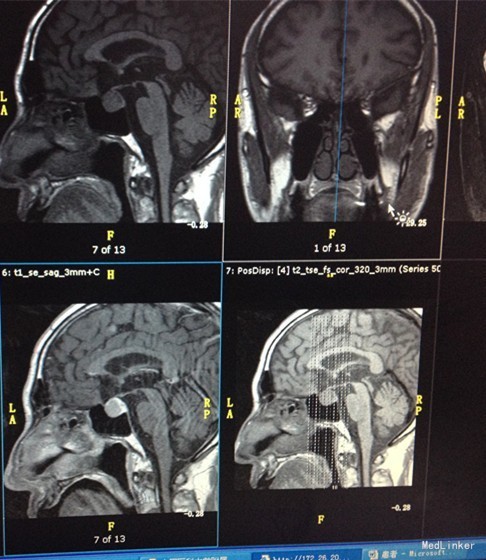

入院查体:颜面潮红,双眼球突出,突眼度为12mm>98mm<13mm,上睑挛缩,睑裂增宽,Stellwag征阴性,von Graefe征阴性,Joffroy征阴性,Mobius征阴性。手细震颤阳性。甲状腺Ⅲ度大,质硬、无压痛、未触及结节,双叶可触及细震颤、可闻及血管鸣。心率69次/分、心律不齐、第一心音亢进、各瓣膜区未闻及病理性杂音。 辅助检查::ALP 161U/L,GGT 151U/L,ALB 38.9g/L,BNP 1053pg/ml。心电图:心房颤动。尿常规示蛋白质PRO微量。血浆B型钠脲肽(BNP)2029pg/ml。血清肌酸激酶同工酶MB2.60ng/ml。 OGTT及胰岛功能: 0 30 60 120 180 葡萄糖 4.31 7.45 10.1 11.33 7.11 C肽 517.22 1080.45 1651.7 2392.71 2018.07 胰岛素 6.58 21.32 21.18 27.57 14.91 血清尿酸429umol/L。I型胶原羧基端肽β特殊序列623.40pg/ml,血清骨钙素18.14ng/ml。FT4 25.5600pmol/L,FT3 6.9800pmol/L,TSH 2.2596mIU/L。血浆糖化血红蛋白6.00%。肾上腺皮质激素系列(8:00):血浆促肾上腺皮质激素48.76pg/ml,血浆皮质醇451.60nmol/L。促性腺激素系列:血清促卵泡刺激素12.40mIU/mL。血清泌乳素320.00mIU/L。血清生长激素测定GRH4.62mIU/L。血清甲状腺结合球蛋白13.40ug/ml,血清甲状腺球蛋白>300.00ng/mL。血清脱氢表雄酮及硫酸酯1.93umol/L,血清游离睾酮33.57pmol/L,性激素结合球蛋白115.00nmol/L。垂体MR平扫+增强,诊断意见:鞍区占位性病变,垂体瘤可能大。 奥曲肽抑制试验: 0 2h 4h 6h 8h 24h TSH 2.14 1.77 1.48 1.32 1.19 0.48 FT3 7.5 7.4 7.74 7.11 6.8 5.76 FT4 25.44 23.7 23.89 23.3 22.64 21 PRL 214 214 212 208 207 312 甲状腺彩超示甲状腺体积增大,向胸骨后方生长;甲状腺回声,不除外桥本病;结甲液性变钙化;双颈部淋巴结肿大,超声结构正常。心彩超示全心大,双房显著;二尖瓣病变(前叶脱垂,返流中度);肺高压(重度),三尖瓣返流(中度);下腔静脉增宽,提示右房压力增高;主动脉瓣退行性变伴轻-中度返流;静息状态下左室整体收缩功能正常低值,射血分数53%。甲旁素骨钙系列示血清甲状旁腺激素4.66pmol/L,血清降钙素2.22pmol/L,血清骨钙素16.79ug/L。

诊断:垂体肿物(TSH瘤可能性大) 甲状腺功能亢进症 甲状腺结节 心律失常 心房颤动 心功能不全 2型糖尿病 高血压病2级(极高危组) 高尿酸血症 治疗:针对垂体肿物,予生理盐水1ml+注射用奥曲肽0.1g每日2次(早9点,晚21点)肌肉注射,1周后序贯善龙20mg每月1次肌肉注射,1个月后复查甲功甲炎,3个月后复查垂体MR+增强。针对心房颤动等,间断给予呋塞米、螺内酯、拜阿司匹灵、倍他乐克缓释片、异乐定口服。予蒙诺片降压,百赛诺保肝